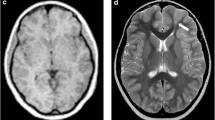

Two nuclear radiologists, blinded to patient history and acquisition time, independently rated the subjective PET image quality using a 5-point Likert scale. The scale ranged from 1 (non-diagnostic) to 5 (excellent), with 1 being undiagnosable, 2 being considered inadequate diagnosis, 3 being considered acceptable for diagnosis, 4 being considered better than the average, and 5 being considered optimal. Examples of grades 5 − 3 (5: excellent, 3: fair) were illustrated in Fig. 1.

18F-FDG PET image of an 11-year-old female patient weighing 43 kg, who had been diagnosed with gangliocytoma by pathology, was reconstructed into brain axial views of 600, 300, 150 and 60 s (a–d). The overall image scores for the groups of 600, 300, 150, and 60 s were 5, 5, 4, and 3, respectively. (e) Histopathology finding of the patient, characterized by a mixed population of neoplastic glial cells and dysplastic neurons